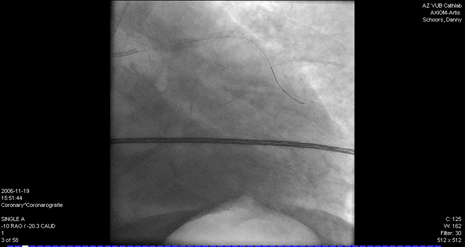

3. L’appareil à rayons X fait des clichés des coronaires selon différents angles et les images s’affichent sur les moniteurs. Le cathéter guide et le fil guide sont tous deux bien visibles sur le moniteur.

Avant (figure 1) et après (figure 2) la dilatation